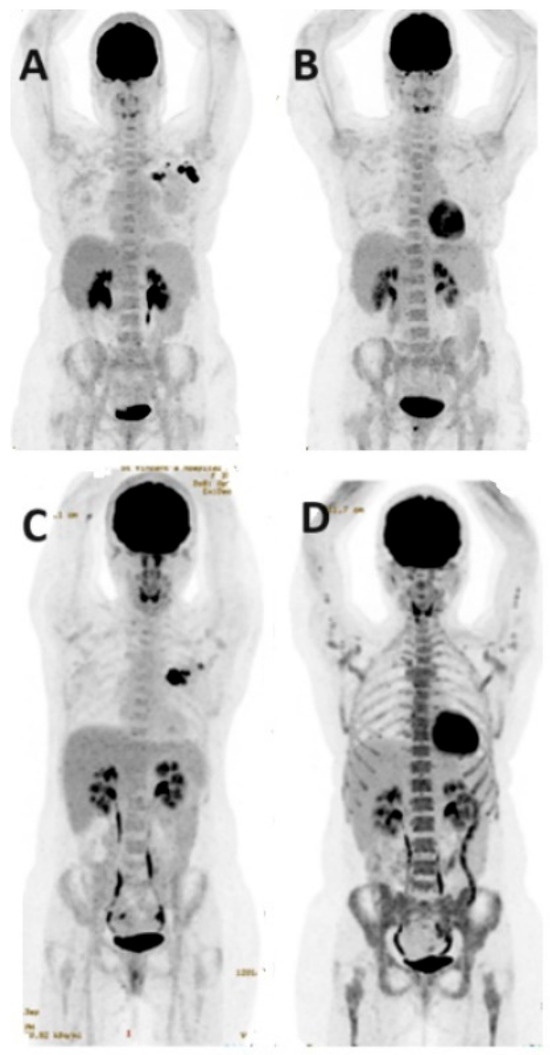

- Hildebrandt, M.G.; Naghavi-Behzad, M.; Vogsen, M. A role of FDG-PET/CT for response evaluation in metastatic breast cancer? Semin. Nucl. Med. 2022, 52, 520–530. [Google Scholar] [CrossRef] [PubMed]

- Suto, H.; Inui, Y.; Okamura, A. Is CT or FDG-PET more useful for evaluation of the treatment response in metastatic HER2-positive breast cancer? A case report and literature review. Front. Oncol. 2023, 13, 1158797. [Google Scholar] [CrossRef] [PubMed]